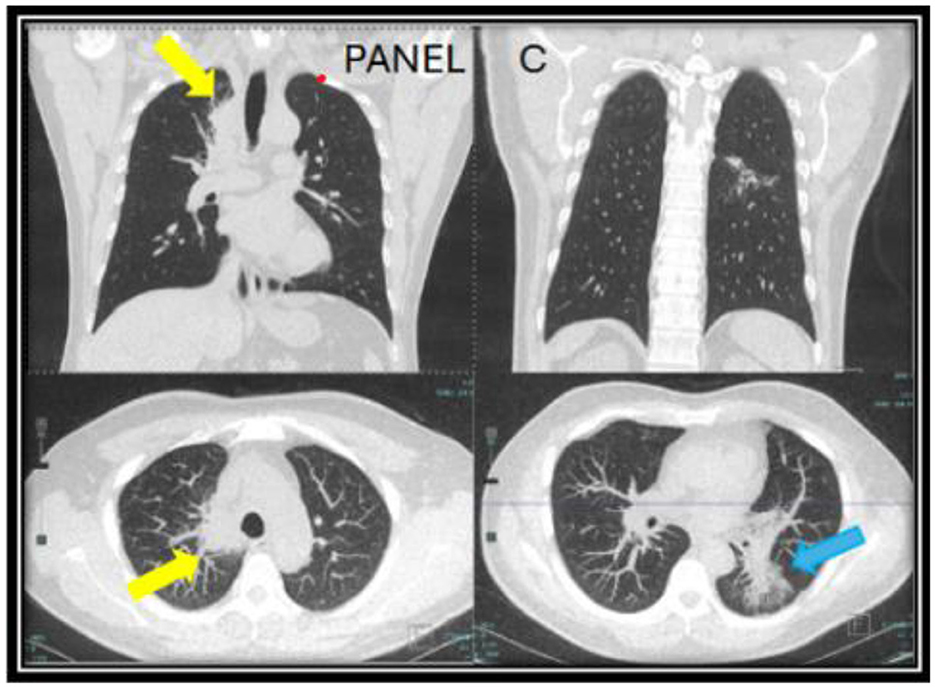

However, the patient expressed concerns about a new onset dry cough a year later. He was urged to present to the clinic for a clinical workup, but he did not follow up for 6 months. When he presented to the clinic, he continued to endorse persistent symptoms of dry cough and shortness of breath. A CT chest revealed a new right upper lobe infiltrate, and the patient's Coccidioides CF titer had spiked to 1:64 (Figure 2). Recognizing this as a relapse of pulmonary coccidioidomycosis, the patient was promptly restarted on itraconazole, which resulted in dramatic resolution of symptoms within 2 weeks. With initiation of itraconazole, the patient's ruxolitinib dose was again reduced to PO 5 mg BID. Follow-up testing showed a steady decline in CF titers to 1:4, confirming the effectiveness of continued antifungal therapy. Repeat CT imaging revealed resolution of right upper lobe infiltrate after 2 years of itraconazole use (Figure 3). At the time of publication of this paper, the patient has continued to maintain effective disease control on itraconazole and ruxolitinib and will continue with indefinite antifungal treatment.

Figure 2. CT chest images taken a year after of being off of itraconazole (year two) when the patient developed a new persistent cough associated with a rise in Coccidioides complement fixation titers. A new mass-like consolidation of the medial right lung apex measuring 5.1 × 2.9 × 0.8 cm (yellow arrow) was noted. The superior segment of the left lower lobe continued to improve (blue arrow). The nodular consolidation has decreased, and mild scarring and bronchiectasis now persisted in this area (C).